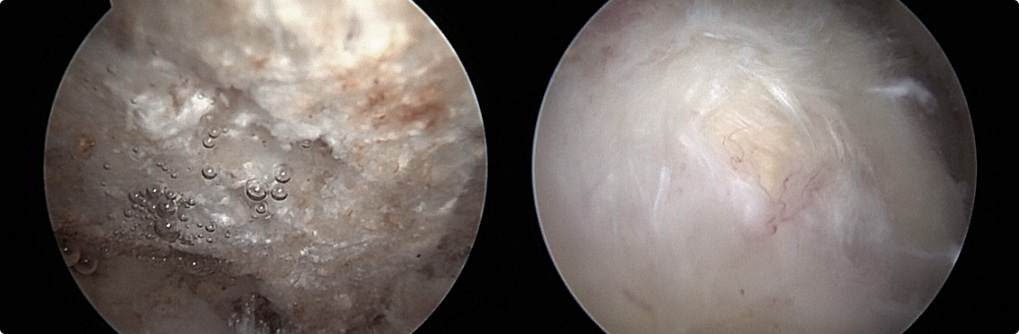

관절 내시경을 통한

견봉 성형술

관절 내시경을 통하여

힘줄 손상을 유발하는 견봉하 골극을 제거합니다.

이러한 경우

내시경 시술을

고려합니다.

보존적 치료에 호전되지 않는 경우

회전근개 파열로 진행되고 있는 경우

극심한 통증을 동반하고 있는 경우